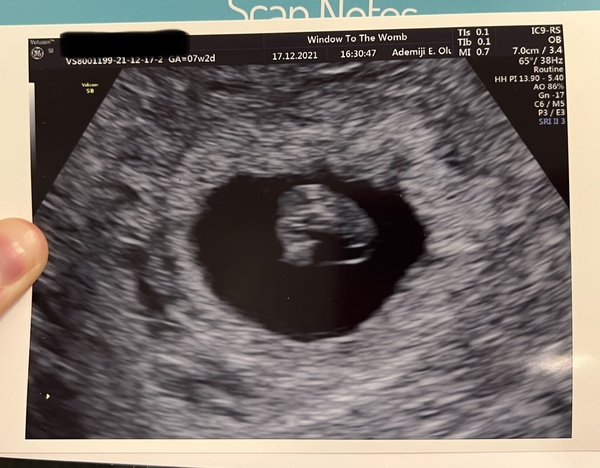

Cleozeta · 17/12/2021 16:35

Luckyfamilymum · 17/12/2021 19:54

Everything is in the right place, LMP has me at 7+2 but I was dated 7 so I’m happy with that :)

That little heartbeat on the screen was just beautiful! I was so worried before hand & convinced there would be something wrong… but no need :)